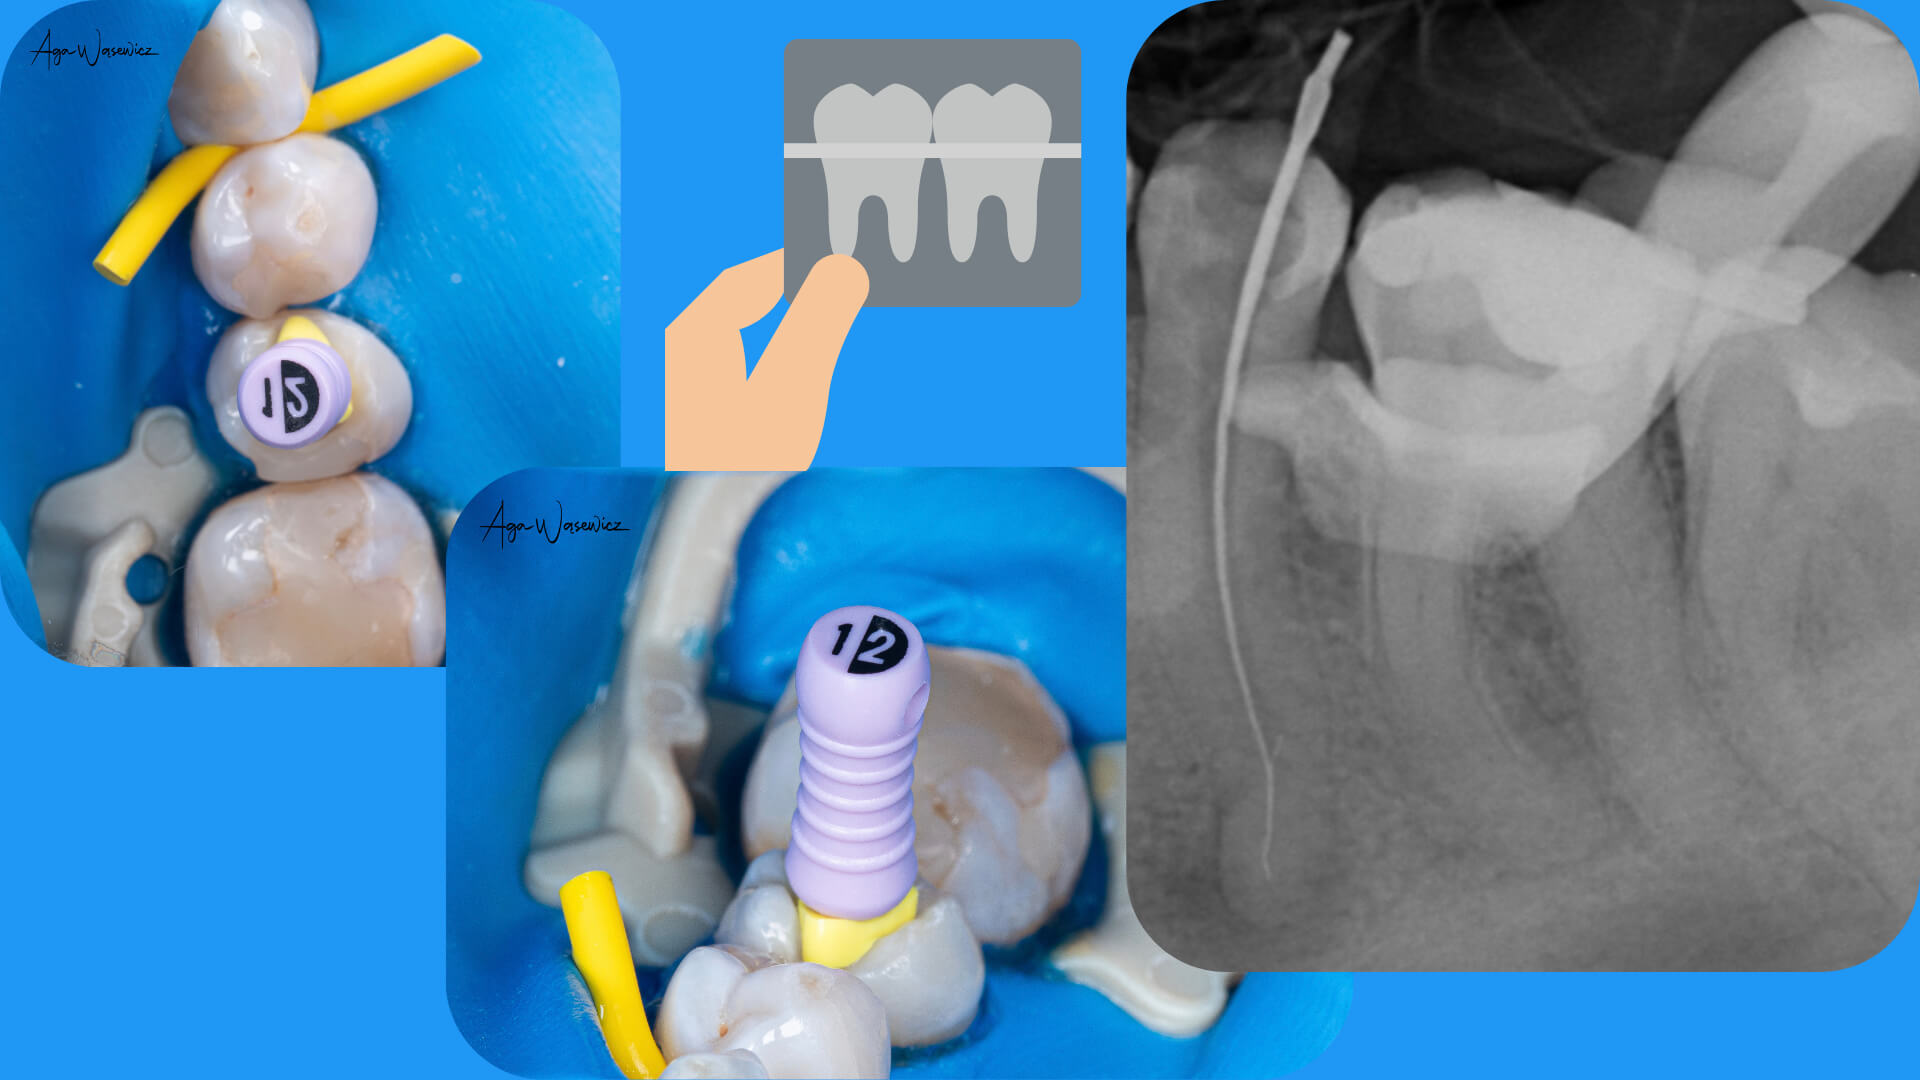

Złamane narzędzie w kanale – jak tego uniknąć i co zrobić, gdy już się stanie?